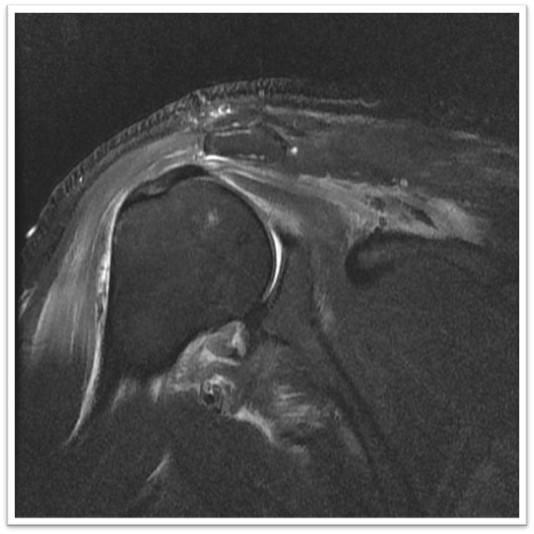

MRI와 초음파를 다시 검토했습니다.

회전근개 극상건의 관절면측(articular-side) 부분파열.